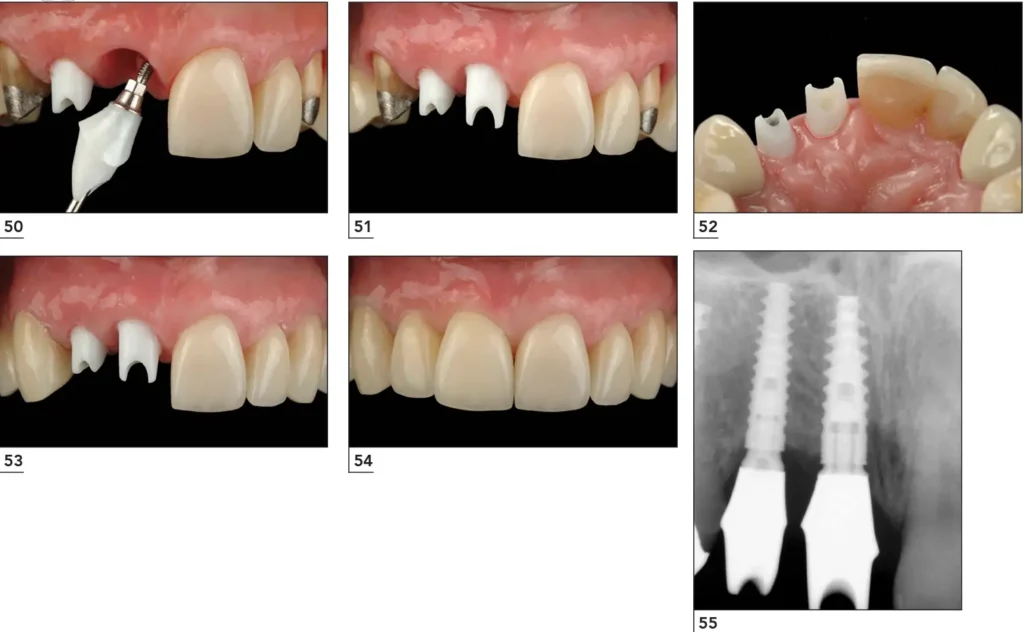

7. Mechanical complications

Occur after the implant is in function.

Examples:

- Screw loosening

- Crown fracture

- Abutment fracture

Main causes are improper prosthetic design or incorrect force distribution.